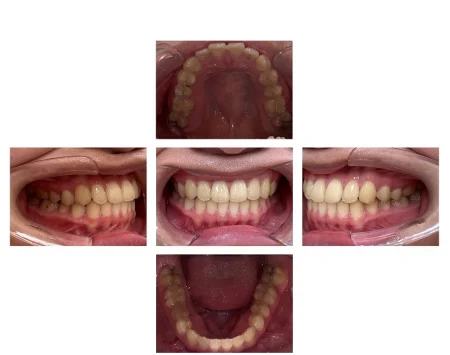

上下の前歯が正常な位置関係になり、美しい歯並びになりました。噛み合わせも問題ありません。

患者様にも「笑ったときに見た目が気にならなくなった」と非常にご満足いただいております。